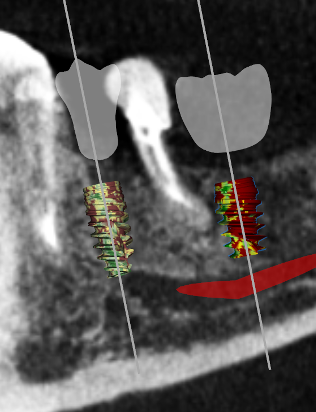

A healthy 60-year-old female presented for an emergency evaluation because she was experiencing pain associated with tooth No. 20. It was mobile, malposed, and given a diagnosis of irreversible pulpitis. In addition, teeth Nos. 19 and 21 had been missing for more than 5 years. After the evaluation, a discussion revealed that the patient desired implant reconstruction of the lower left quadrant. During this initial visit, a CBCT scan was obtained, and the virtual restoration-driven implant planning was completed, confirming that extraction of tooth No. 20 with robot-assisted immediate implant placement at the sites of teeth Nos. 19 and 21 was a viable option (Figure 9 through Figure 13). Splint placement, CBCT capture of the fiducial array, calibration, and landmark confirmation were completed as described in the first case report. Following the administration of intravenous sedation and local anesthesia, tooth No. 20 was atraumatically extracted. Flap access was obtained from the site of tooth No. 18 to the site of tooth No. 22, and robot-assisted surgical implant placement was completed at the sites of teeth Nos. 19 and 21. Intraoperatively, guide pins were placed to evaluate the position of the proposed osteotomies, and it was determined that both implants should be tilted buccally by 0.4 mm. The necessary changes were made in the software application, and the new implant placement plan was immediately ready for robotic implementation. The implants were robotically delivered to their planned positions at the sites of teeth Nos. 19 and 21 and torqued to initial stability at 50 Ncm and 45 Ncm, respectively (Figure 14 and Figure 15). Healing abutments were placed, and the tissue was closed primarily. In this case, robotic assistance facilitated the performance of surgery on the same day that the patient initially presented and permitted intraoperative modifications to be made.

(9.) Virtual plan showing that the extraction of tooth No. 20 followed by robot-assisted immediate implant placement at the sites of teeth Nos. 19 and 21 was a viable option.

Figure 9

(11.) Implant position at site No. 21 optimized on the virtual plan.

Figure 11

(12.) Postoperative CBCT image of actual implant placement at site No. 21.

Figure 12

(13.) Postoperative CBCT image of actual implant placement at site No. 19.

Figure 13